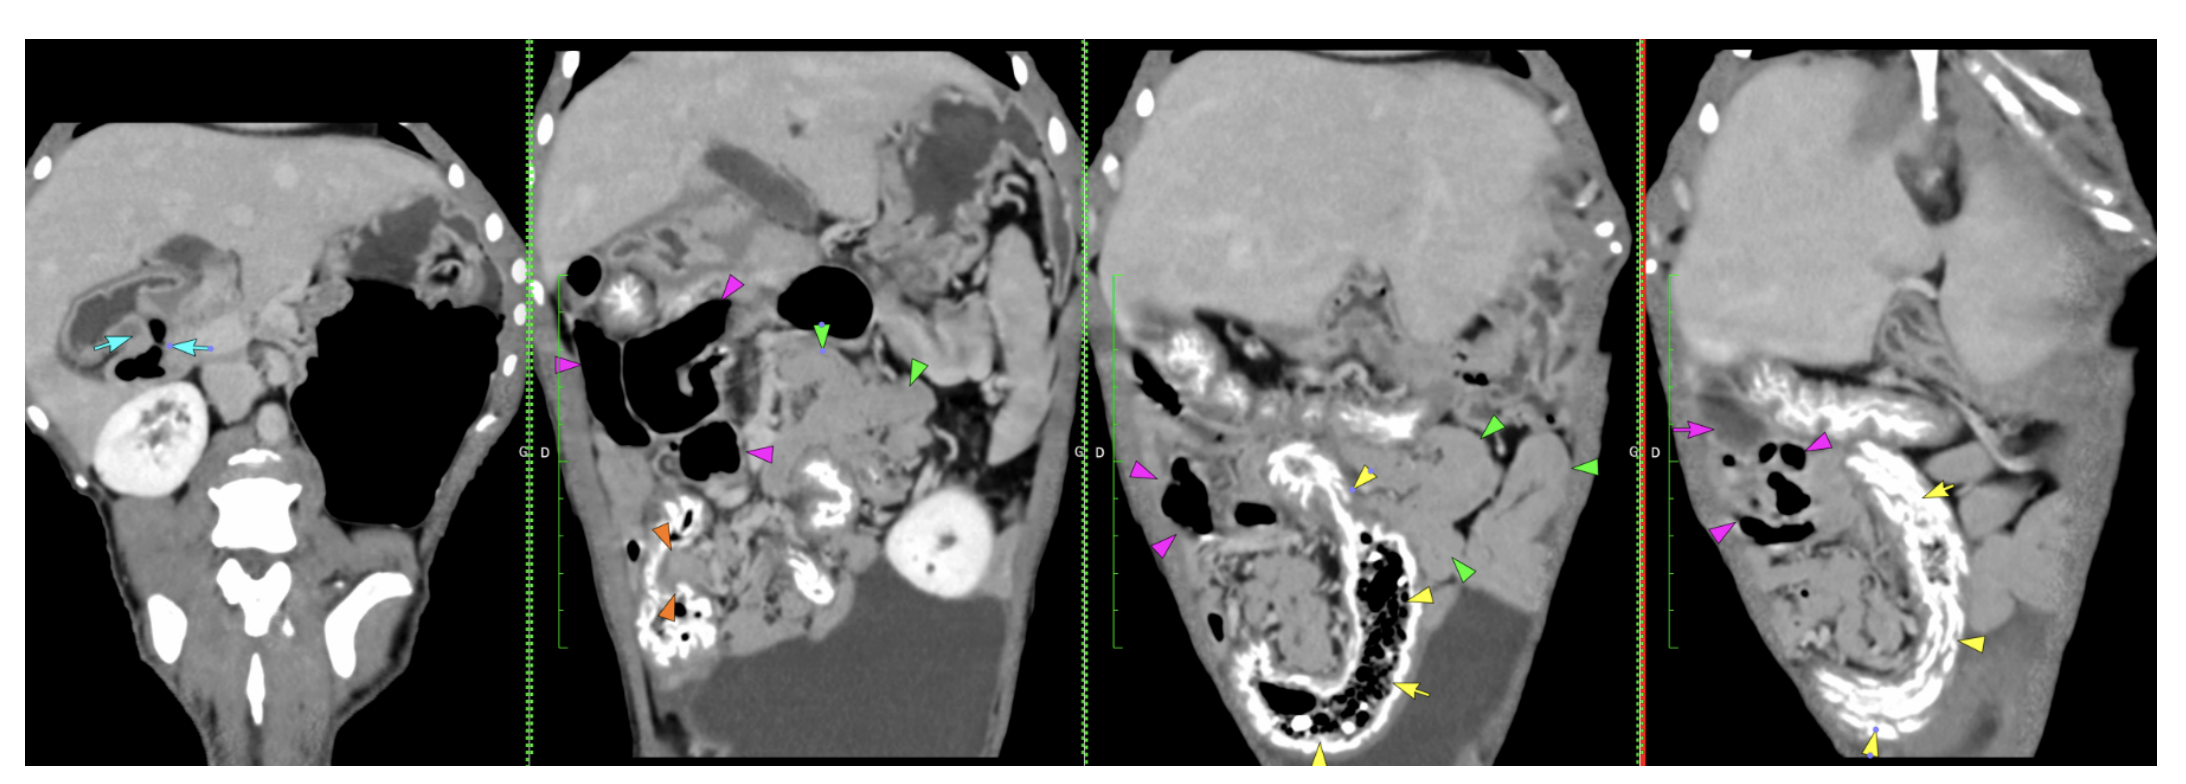

The stomach is moderately distended with gas and a small amount of fluid. The pylorus is well defined. Some gas bubbles are seen just after the pylorus (blue arrows), then the duodenum is rather poorly filled and difficult to completely follow.

A small to medium amount of gas and fluid is seen accumulating in the jejunum in the right mid-abdomen (pink arrows), but it seems to get to a normal size on both sides without evidence of luminal obstructive foreign material. The rest of the jejunum is rather prominent but almost empty (green arrows).

The ileocaecal junction is well seen (orange arrows). Mineral coating is seen all along the caecum and colon (previous barium study versus mineral oral coating).

Some gas-mixed feces are seen in the caecum (yellow arrows), the colon is almost empty, partially multifocally gas-distended.

I discussed this case with my colleague, as there is a doubtful region in the right mid-abdomen. We cannot delineate luminal foreign material, and the distension remains moderate while the rest of the gastrointestinal tract is rather empty. We suspect gastroenteritis given the absence of a clear obstruction. An infiltrative pathology with mild thickening is also possible, but it would not fit the acute clinical signs.